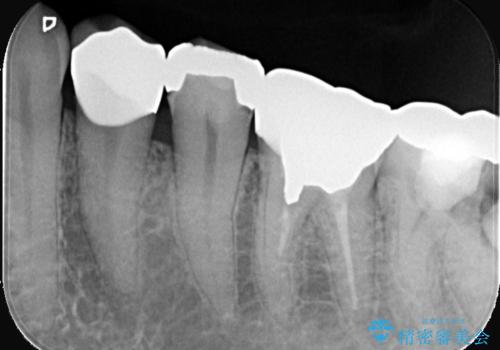

- 左下4番の奥歯に、歯肉の下まで進行した深い虫歯を認め来院されました。通常であれば神経を抜く必要があるほど深い虫歯でしたが、患者様の歯をできる限り保存するため、歯の神経を抜かずに残すことを目指す治療計画を立案。歯肉の下にある虫歯を適切に治療するため、歯周外科処置で歯肉のラインを調整した上で、精密なセラミッククラウンで修復することになりました。

まず、虫歯を徹底的に除去するために、歯周外科処置で歯肉のラインを調整し、治療部位を露出させました。その後、神経に近接した深い虫歯を慎重に除去。神経の保護処置を施し、歯の神経を抜くことなく保存することができました。型取りから、患者様の歯の色や形に合わせたオーダーメイドのセラミッククラウンを作製。最終的に、精度の高いクラウンを装着し、咬み合わせを細かく調整しました。これにより、神経を温存しながら、虫歯の再発を防ぎ、快適な咬み心地を取り戻していただけました。